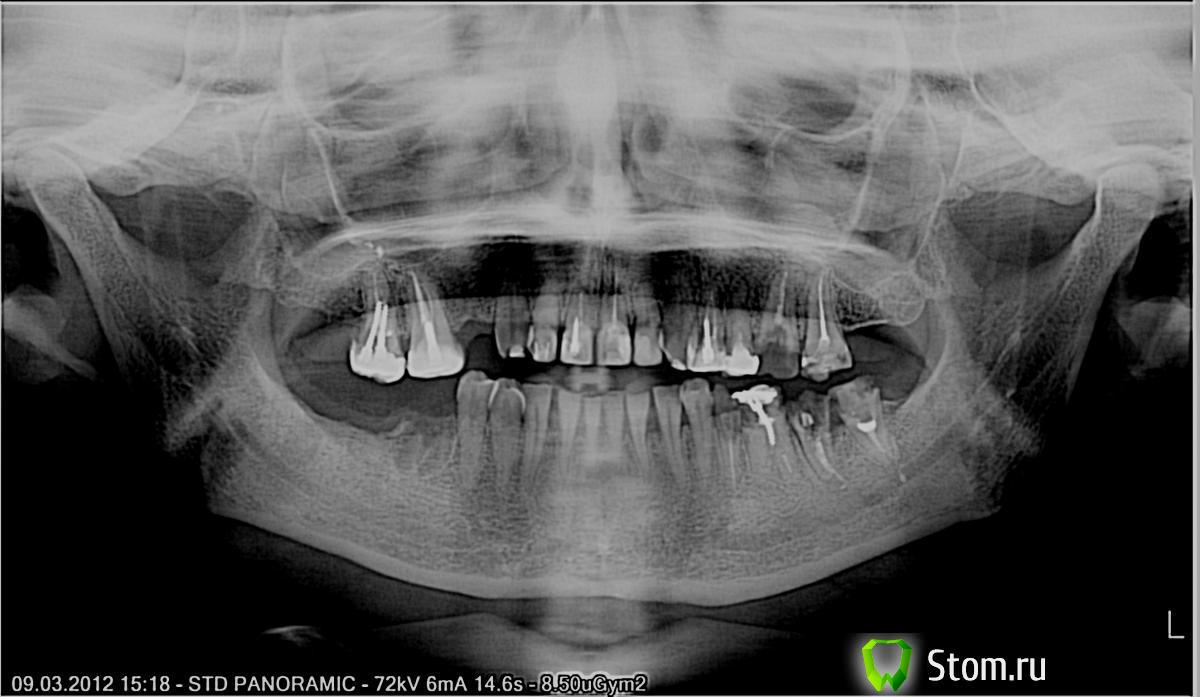

balashovat Опубликовано 10 марта, 2012 Поделиться Опубликовано 10 марта, 2012 Здравствуйте.Помогите мне, пожалуйста, с подготовкой к протезированию. Летом планирую поехать в Беларуссию для протезирования + установки имплантов.Сейчас хочу подготовиться, удалить зубы, которые не подлежат восстановлению и что-то перелечить при необходимости. Меня особенно беспокоит, что делать с двумя сильно разрушенными зубами:37 зуб - недавно выпала огромная пломба вместе со штифтом, осталась одна стенка, которая шатается. Остальная часть зуба на 5 мм ниже десны. Обязательно ли его удалять или можно удалить только стенку, на корень поставить коронку?26 зуб - тоже осталась одна стенка, остальная часть зуба вровень с десной или чуть глубже. Удалять его не хотелось бы. Спасибо заранее. http://s019.radikal.ru/i609/1203/3e/2284db208fa2t.jpg Ссылка на комментарий

Doc Опубликовано 13 марта, 2012 Поделиться Опубликовано 13 марта, 2012 Я бы не сказал, что у Вас проблемы с этими двумя зубами. Я бы сказал, что у Вас всего пара зубов, с которыми нет проблем. Даже в Москве найти врачей, которые сделали бы тут все грамотно - нужно будет постараться. Работы тут полно и надолго, займет не то что не один месяц, а может и год. Ну а в Белоруссии найти такого уровня коллег будет еще сложнее. Впрочем, дешевые районные поликлиники у них, думаю, не хуже, чем у нас и прогноз одинаковый. Так что удачи. 1 Ссылка на комментарий

Salma Опубликовано 13 марта, 2012 Поделиться Опубликовано 13 марта, 2012 Скорее всего придется проститься с зубами 26,35,36,37,возможно 17. Разбираться с 16,27,38 и верхними передними зубами. 1 Ссылка на комментарий

FBR Опубликовано 21 марта, 2012 Поделиться Опубликовано 21 марта, 2012 Добрый день. То что касается удалений:1. Удаление 17,26,35,36,37,38.2. Перелечивание 16,11,21,22,24,25,27 с подготовкой под коронки. 1 Ссылка на комментарий